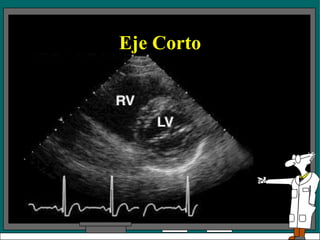

Eje corto Hay 4 posiciones del transductor para los exámenes en eje corto del VI. El plano l da una vista de la punta del corazón La posición 2 es una vista a nivel de los músculos papilares. El plano 3  esta a nivel de la válvula mitral. El plano cuatro da una vista a nivel de la válvula aórtica.

Eje Corto El espacio intercostal es el mismo para los planos 2, 3 y 4. El examen en el plano 1 requiere mover el transductor a un espacio intercostal inferior

Eje corto Hay4 posiciones del transductor para los exámenes en eje corto del VI. El plano l da una vista de la punta del corazón La posición 2 es una vista a nivel de los músculos papilares. El plano 3 esta a nivel de la válvula mitral. El plano cuatro da una vista a nivel de la válvula aórtica.

Eje Corto Elespacio intercostal es el mismo para los planos 2, 3 y 4. El examen en el plano 1 requiere mover el transductor a un espacio intercostal inferior